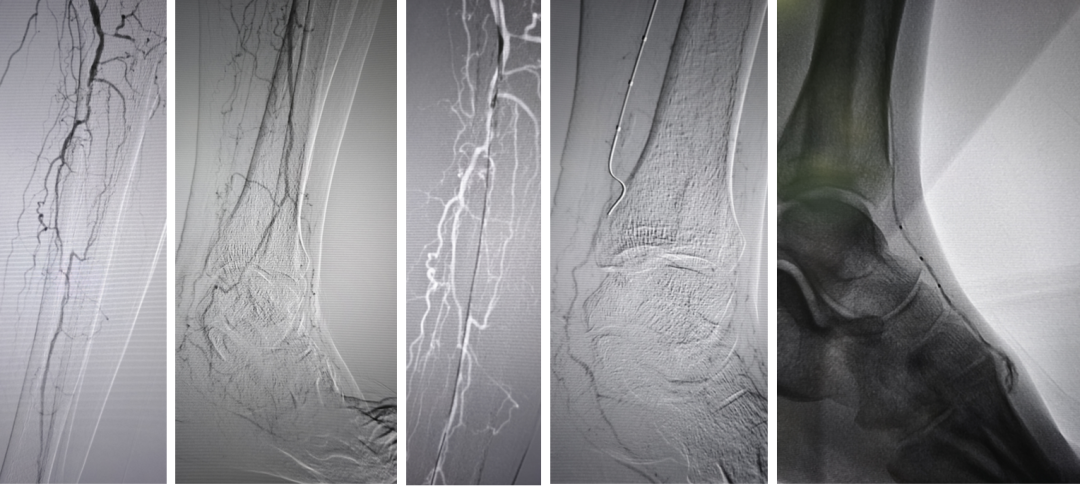

★ 导丝对吻技术与CART技术

当逆向导丝无法进入正向真腔时,可采用导丝对吻技术:将逆向导丝留置作为标记,引导正向导丝前进。若两者均在假腔内,则可应用球囊扩张假腔(CART或Reverse-CART),为导丝进入真腔创造条件。

Case 5:正向导丝经胫前进入,逆向导丝经足底上行,在踝部无法汇合。先后扩张正向球囊和逆向球囊后,导丝顺利进入同一腔道,成功开通足弓。

Case 6:采用双球囊对吻技术:正向使用外周球囊,逆向使用冠脉球囊,在6F鞘内同时扩张2mm重叠段,导丝顺利通过。